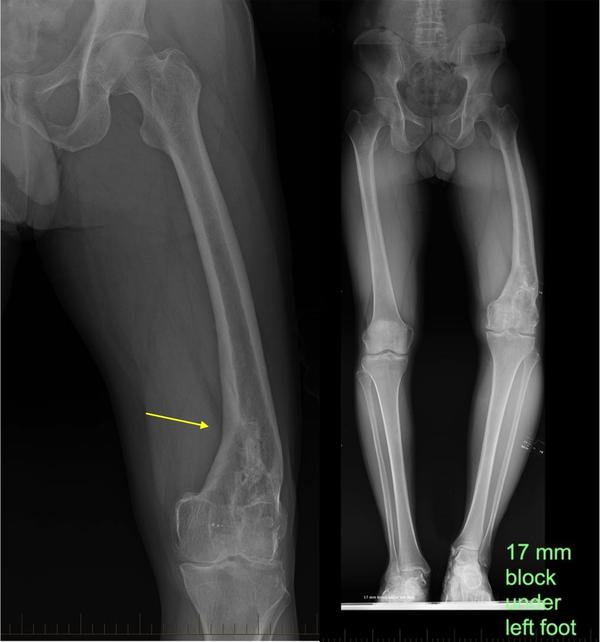

Partial Knee Replacement

Partial Knee Replacement in Jaipur – The Derma Joint Co Knee pain due to arthritis or localized joint damage can limit mobility and reduce quality of life. Partial knee replacement (PKR) is a surgical procedure that replaces only the damaged compartment of the knee while preserving healthy bone and tissue. At The Derma Joint Co, recognized as the best partial knee replacement surgeon in Jaipur, we provide advanced surgical care, precise techniques, and personalized treatment to restore knee function and relieve pain. What is Partial Knee Replacement? Partial knee replacement involves replacing only the affected compartment of the knee (medial, lateral, or patellofemoral) while keeping the healthy parts intact. This procedure is ideal for patients with: Osteoarthritis limited to one part of the knee Localized cartilage damage Knee pain that has not responded to medications or physiotherapy Desire for quicker recovery with minimal surgical intervention Symptoms Indicating the Need for Partial Knee Replacement Persistent knee pain affecting daily activities Stiffness and reduced range of motion Swelling or tenderness in the affected compartment Difficulty walking, climbing stairs, or standing for long periods Chronic pain not relieved by non-surgical treatments Advanced Partial Knee Replacement at The Derma Joint Co At The Derma Joint Co, we provide comprehensive care for partial knee replacement: Accurate Diagnosis – X-rays, MRI, and clinical assessment to identify affected compartments Customized Surgical Planning – tailored prosthesis selection and surgical approach Advanced Surgical Techniques – precise implant placement preserving healthy tissue Post-Surgery Rehabilitation – physiotherapy and exercises for faster recovery and mobility Long-Term Monitoring – regular follow-ups to ensure proper function and prevent complications Why Choose The Derma Joint Co for Partial Knee Replacement in Jaipur? Experienced orthopedic and knee replacement surgeons State-of-the-art surgical facilities and tools Personalized care plans based on patient’s condition Safe, hygienic, and patient-centered clinic environment Trusted as the best partial knee replacement surgeon in Jaipur Tips for Faster Recovery Follow post-surgery physiotherapy and rehabilitation programs Maintain a healthy diet rich in protein and calcium Avoid high-impact activities during early recovery Attend all follow-up appointments for proper monitoring Gradually resume mobility under professional guidance Conclusion Partial knee replacement is an effective solution to relieve pain, restore function, and improve quality of life for patients with localized knee damage. At The Derma Joint Co – the best partial knee replacement surgeon in Jaipur, we provide expert surgical care, personalized rehabilitation, and dedicated follow-up to ensure optimal outcomes. 👉 Book your consultation today at The Derma Joint Co and receive specialized care for partial knee replacement.

Total Knee Replacement

Total Knee Replacement in Jaipur – The Derma Joint Co Knee pain from severe arthritis, injury, or degeneration can significantly affect mobility and quality of life. Total knee replacement (TKR) is a highly effective surgical procedure that replaces damaged knee joint surfaces with advanced prosthetics, restoring function and reducing pain. At The Derma Joint Co, recognized as the best total knee replacement surgeon in Jaipur, we provide expert care, advanced surgical techniques, and personalized treatment plans to help patients regain mobility and independence. What is Total Knee Replacement? Total knee replacement involves removing damaged cartilage and bone from the knee joint and replacing it with a durable prosthetic implant. This procedure is recommended for: Severe osteoarthritis Rheumatoid arthritis Post-traumatic arthritis Deformities or loss of knee function due to injury or disease Symptoms Indicating the Need for Total Knee Replacement Severe, persistent knee pain affecting daily activities Stiffness and limited range of motion Swelling or tenderness in the knee joint Difficulty walking, climbing stairs, or standing for long periods Chronic knee pain not relieved by medications or physiotherapy Advanced Total Knee Replacement at The Derma Joint Co At The Derma Joint Co, we provide comprehensive care for total knee replacement: Accurate Diagnosis – clinical evaluation, X-rays, and MRI scans Customized Surgical Planning – tailored prosthesis selection and surgical approach Advanced Surgical Techniques – precise implant placement for optimal alignment and longevity Post-Surgery Rehabilitation – physiotherapy and exercises to restore mobility and strength Long-Term Monitoring – regular follow-ups to ensure implant function and prevent complications Why Choose The Derma Joint Co for Total Knee Replacement in Jaipur? Experienced orthopedic and knee replacement surgeons State-of-the-art surgical facilities and tools Personalized treatment plans based on patient’s anatomy and condition Safe, hygienic, and patient-focused clinic environment Trusted as the best total knee replacement surgeon in Jaipur Tips for Faster Recovery Follow physiotherapy and post-surgery exercise programs Maintain a balanced diet rich in protein and calcium Avoid high-impact activities during early recovery Attend all follow-up appointments for monitoring and evaluation Gradually resume mobility under professional guidance Conclusion Total knee replacement is a reliable solution to relieve pain, improve mobility, and enhance quality of life. At The Derma Joint Co – the best total knee replacement surgeon in Jaipur, we provide expert surgical care, personalized rehabilitation, and dedicated follow-up to ensure optimal outcomes. 👉 Book your consultation today at The Derma Joint Co and get specialized care for total knee replacement.